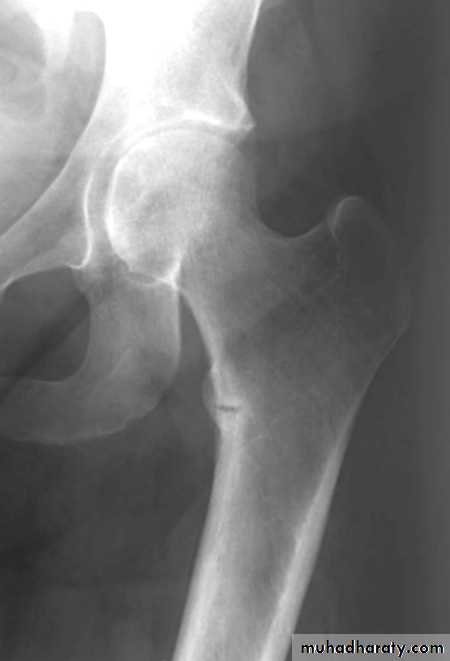

Bone resorption manifest by ostitis fibrosa cystica and subperiosteal resorption.

metabolic bone disease

hyperparathyroidism